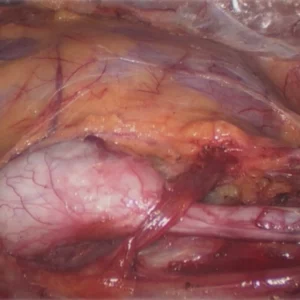

The mainstay of treatment of acute pyelonephritis is antibiotics, analgesics, and antipyretics. Nonsteroidal anti-inflammatory drugs (NSAIDs) work well to treat both pain and fever associated with acute pyelonephritis. In severe cases hospitalisation might be required.